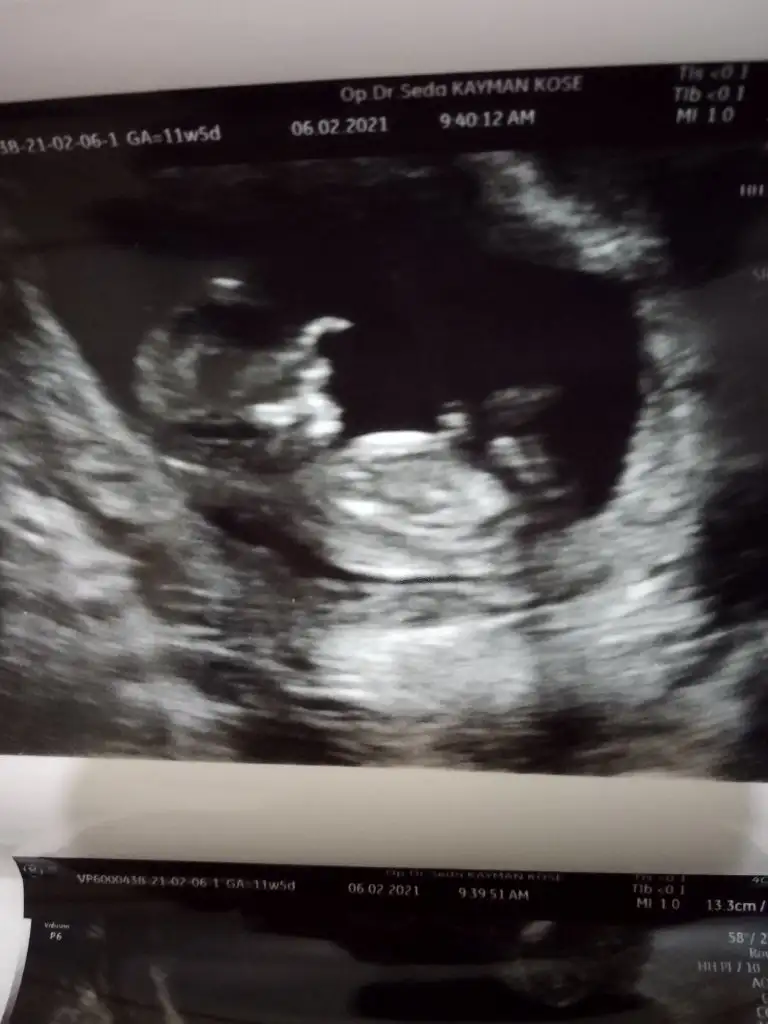

Evet doktorda erkek gibi görüyorum dediErkek gibi sanki diyorumönceki usglerde kız sanki demiştim

Buna göre erkek görünüyor ama en iyi 11 12 13 haftalar olmalıMerhabaIkra meyra , benim ultrason görüntülerime de bakabilir misiniz lütfen?

Kız sanki 11 12 13 haftalar olmalıBuda benim bebişim. Tahminde bulunabilen varsa sevinrm. İçime hep erkek doğuyor.